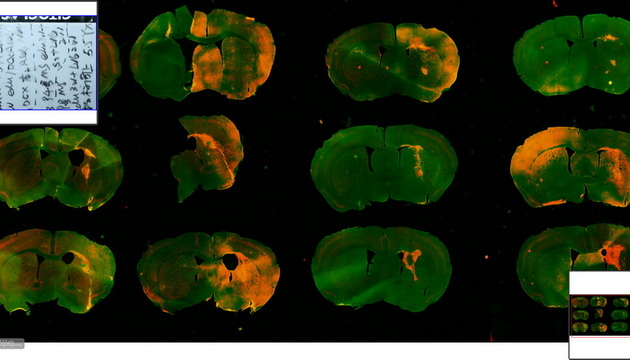

研究等常規熒光觀察需要。 ●研究級熒光觀察方案,研究級倒置熒光MF53-N和研究級正置熒光MF43-N,研究級機身,配備明美MG-120等LED熒光光源,可選配不同的熒光激發塊,半復消色差物鏡對弱信號也有良好的成像能力,滿足FISH、CTC等高要求成像。 ●熒光切片掃描方案,多重熒光數字切片掃描儀MES200,高速全景拼接,精準掃描,助力腦片研究及多重熒光標記分析,推動熒光成像技術發展。